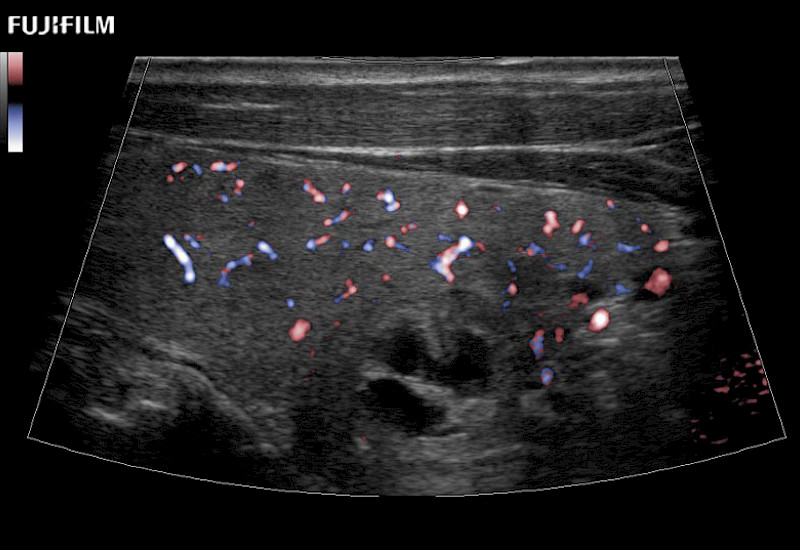

Our dedication to Surgical Oncology allows us to offer superior image quality, outstanding system reliability and intuitive use of cutting edge technology.

The ARIETTA 750 incorporates all of the proven technologies and functions that medical professionals have come to expect from Fujifilm Healthcare.

ARIETTA 750 is the definitive diagnostic ultrasound solution for any clinical setting - Private Office, Imaging Center, or Hospital. The ARIETTA platform provides the ultimate in clinical performance with its state-of-the-art features and large user-friendly display.

The ARIETTA 650 DI combines trusted Fujifilm Healthcare technologies and features tailored for surgical oncology.

Designed to meet the demands of surgeons, the ARIETTA 650 DI offers precise guidance. Its advanced capabilities and large, intuitive display offer accurate and efficient care in operating rooms and specialized surgical settings.